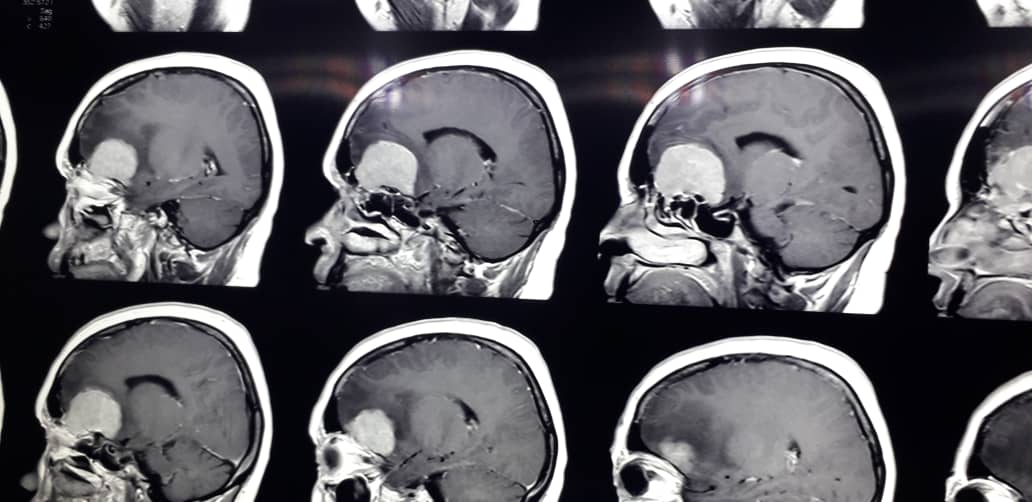

انجام موفقیت آمیز جراحی تومور مغزی بیمار بروجنی

جراحی تومور مغزی بیمار بروجنی با موفقیت انجام شد.

به گزارش خبرگزاری صدا و سیما مرکز چهارمحال و بختیاری،رییس بیمارستان ولی عصر (عج) بروجن، از موفقیت تیم جراحی در خارج نمودن تومور مغزی زن ۴۲ ساله خبر داد. انجام موفقیت آمیز جراحی تومور مغزی بیمار بروجنی

امین احمدی افزود: این بیمار۴۲ ساله به علت تومور مغزی به عوارض سردرد، سرگیجه و کاهش بینایی دچارشده بود.

احمدی گفت: عمل جراحی وی که تومور مغزی در ناحیه قدام(پیشانی) بود به همت دکتر حسینعلی علیخانی و تیمش با موفقیت خارج شد و در حال حاضر حال عمومی بیمار خوب است.

وی گفت: هوشیاری بیمار بازگشته و تاکنون عوارضی در پی عمل جراحی در هیچ کجای بدن وی دیده نشده است.

علیخانی، جراح این بیمار هم گفت: این زن 42 ساله از چند سال پیش دچار کاهش حس بویایی شده ولی ظاهراً به این موضوع اهمیتی نداده است.

وی ادامه داد: از حدود ۴ ماه قبل بیمار دچار سردرد، سرگیجه و کاهش حس بینایی شده و بینایی این بیمار بتدریج کاهش یافته تا جایی که در هفته‌های اخیر نمی‌توانست به درستی ببیند.

وی گفت: با انجام MRI وجود تومور بزرگ وسط مغز این بیمار تایید شد و با توجه به کاهش بینایی وی، بیمار بطور اورژانسی تحت عمل جراحی قرار گرفت.

علیخانی با بیان اینکه در عمل جراحی تومور به صورت کامل از مغز بیمار خارج شد افزود: بینایی این بیمار تقریباً بازگشته و وضعیت وی در حال بهبود است.